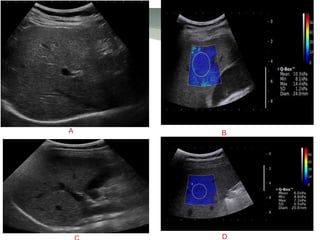

Supersonic shear-wave imaging of a normal and a cirrhotic patient.

A large trapezoidal color box display of the distribution of the elastic properties of

the liver. The severity of stiffness is depicted with the colored look-up table. Dark

blue color represents normal liver tissue (A), and bright blue-green color

represents increased liver stiffness such as liver cirrhosis (B). The round region

of interest (ROI) in the color box is the Q-Box and the mean Young modulus and

standard deviation in the ROI have been calculated

A B